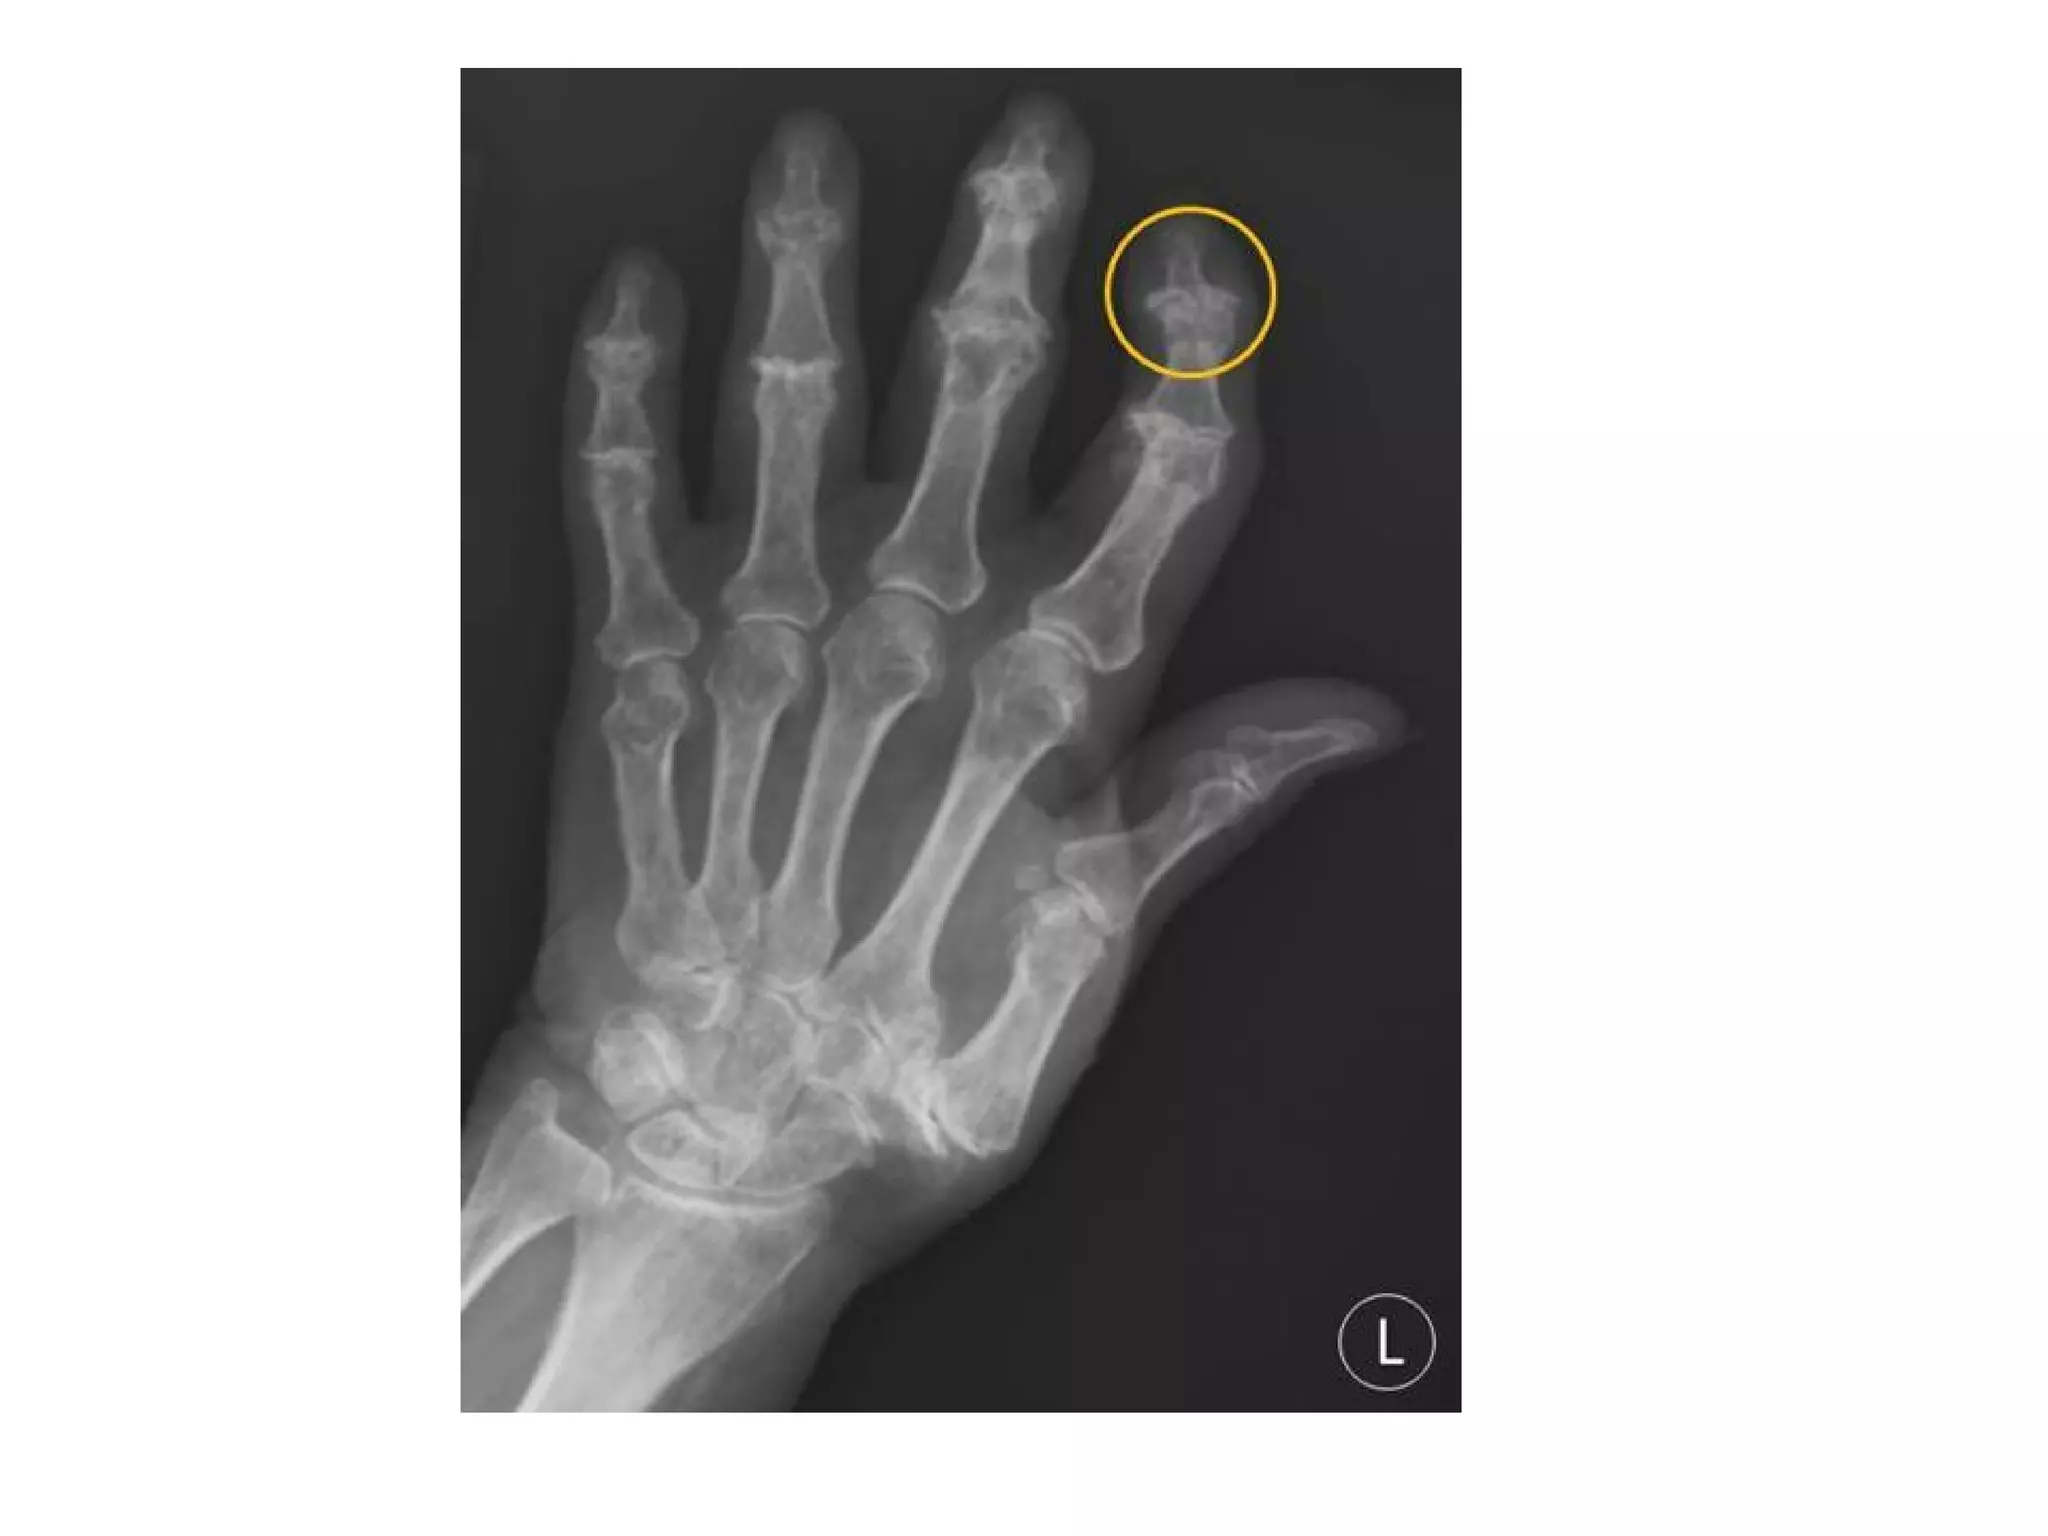

52 year old woman on hemodialysis for 26 years for lupus nephritis

with biopsy-proven dialysis-related amyloidosis , conventional

radiograph shows discrete erosion in lateral aspect of acetabulum

(arrowhead)

Well-defined cystic lesion (arrowhead) with sclerotic rim

(arrows) in superior-posterior left humeral head

Radiolucent lesions of various sizes involving carpal bones (arrows) ,

most have sclerotic margins and some have a lobulated outline , in

carpi , lunate and scaphoid are most often affected